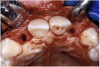

Periapical radiographs were taken to help determine the mesial-distal inclinations of the adjacent tooth roots (Figure 1). The radiographs revealed a serious issue, convergent roots for the right canine and right central, which eliminated that area as a potential implant-receptor site. The space between the left central and canine teeth was minimal, although the roots were relatively parallel. Clinical examination (manual palpation of the root eminences superiorly to the vestibule on the right side) confirmed the root convergence (Figure 2A). The flat, wide zone of the keratinized tissue and lack of interdental papilla was evident for the missing right lateral incisor. There was a marked difference in clinical appearance for the left lateral, which could impact the eventual plan of treatment (Figure 2B). Other significant clinical findings included bilateral facial bone concavities, which existed as a result of the congenitally missing tooth roots. As a diagnostic cue to the underlying bone topography, it is important to follow the demarcation between attached and unattached gingival tissue, and note the crestal width of the available keratinized tissue (Figure 2C).

Figure 2a  Pretreatment buccal views showed (A) root convergence, (B) a difference in clinical appearance of the left lateral, and (C) significant crestal width of keratinized tissue.

Figure 2a

Figure 2b  Pretreatment buccal views showed (A) root convergence, (B) a difference in clinical appearance of the left lateral, and (C) significant crestal width of keratinized tissue.

Figure 2b

Figure 2c  Pretreatment buccal views showed (A) root convergence, (B) a difference in clinical appearance of the left lateral, and (C) significant crestal width of keratinized tissue.

Figure 2c